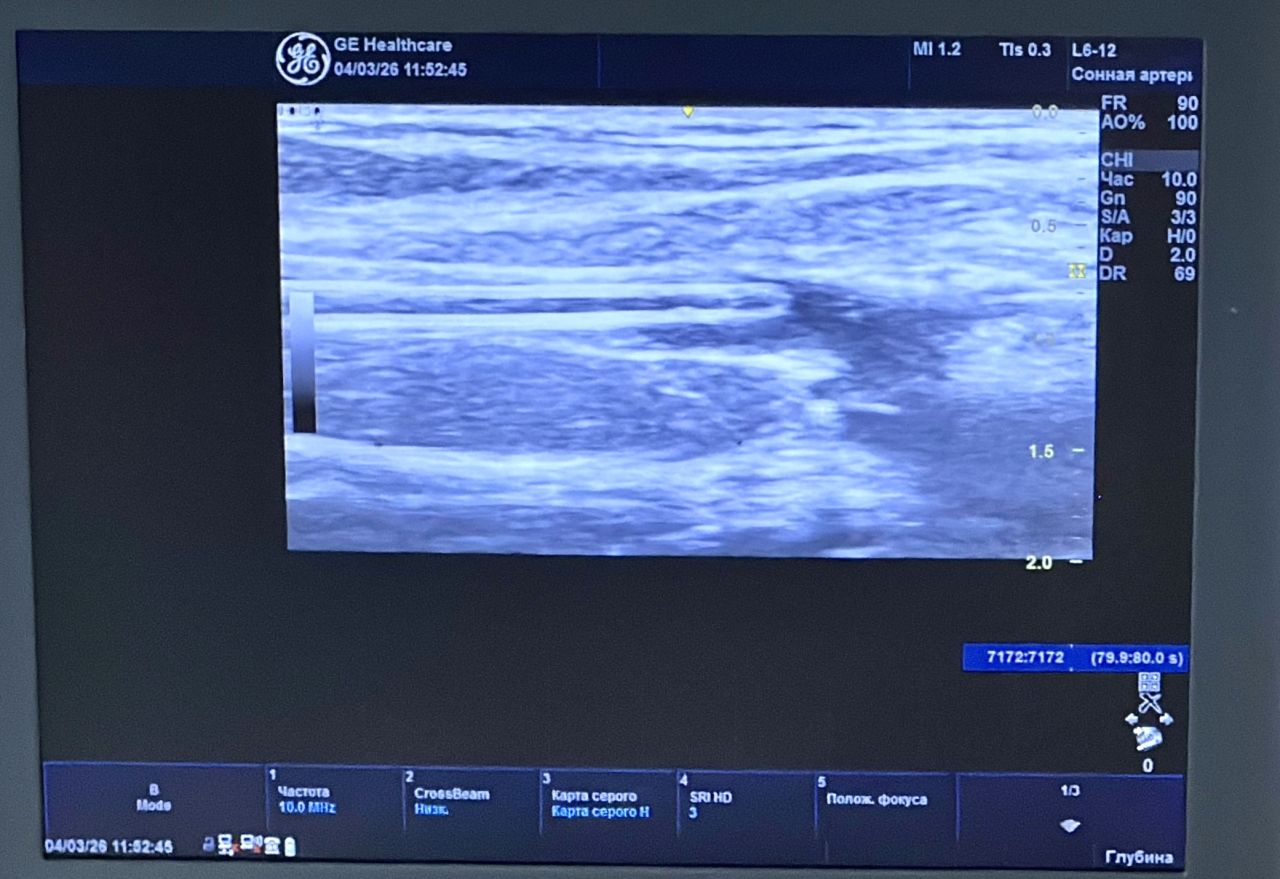

Метод применяется для лечения варикозной болезни и относится к числу наиболее щадящих малоинвазивных технологий. В ходе процедуры под ультразвуковым контролем в поражённую вену вводится специальный медицинский клей, который «запечатывает» сосуд и выводит его из патологического кровотока. Вмешательство выполняется через микропрокол и занимает всего несколько минут.